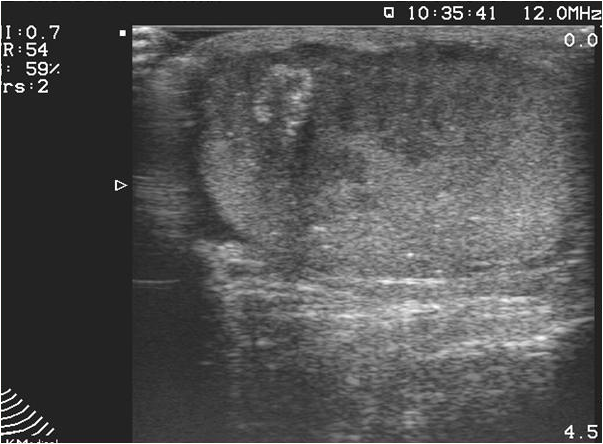

Seminomas typically occur in 30-40 years of age. They are characteristically hypoechoic, 25% of them have already given metastases at the time of diagnosis, which primarily involve the lungs. The serum alpha-fetoprotein levels are usually normal while, beta human chorionic gonadotropin (beta-hCG) is increased. Seminomas are sensitive for chemo- and radiotherapy. The 10-year survival rate is 75-85%.

Image

Figure 10. US image of a seminoma.